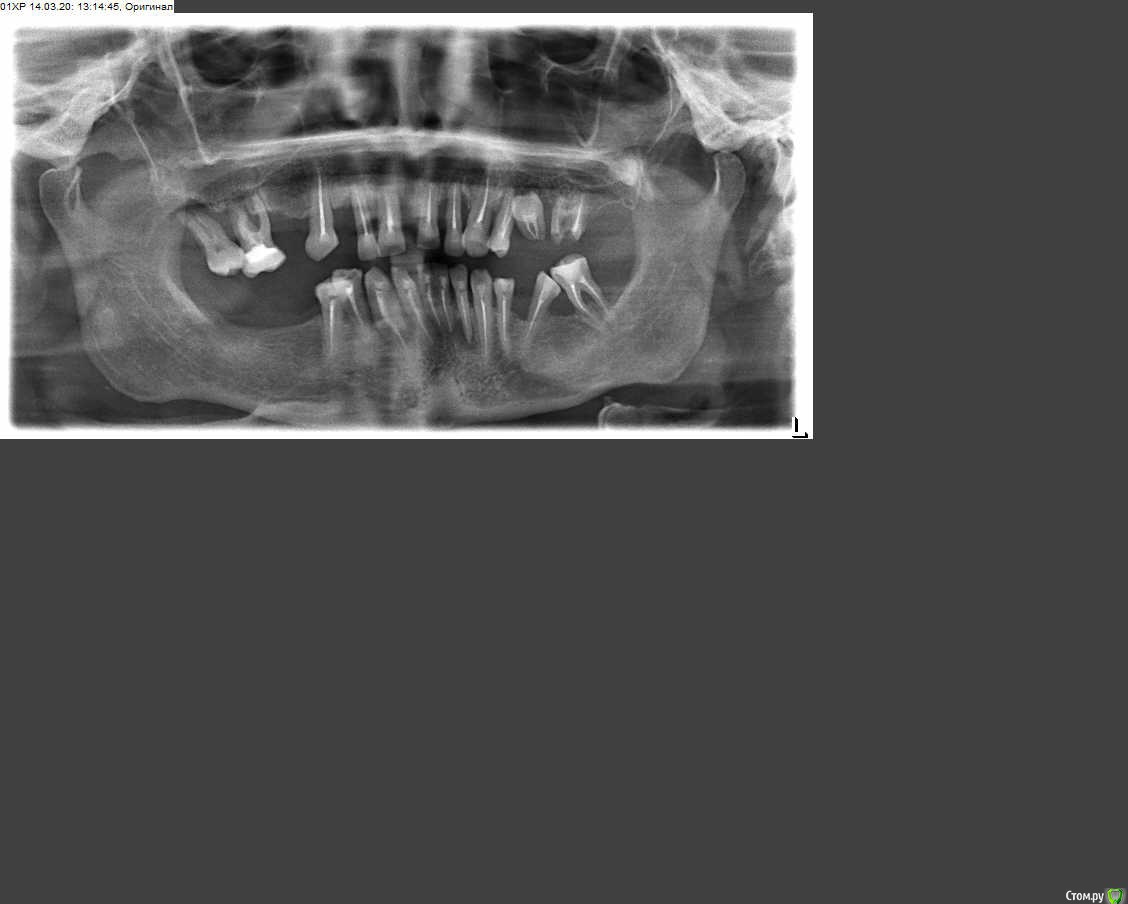

Прошу отозваться специалистов и дать совет. У меня пародонтит, потеряна основная часть зубов. Снимок во вложении. Хочу установить протезы, но не могу определиться с тактикой лечения. Была в нескольких клиниках и все предлагают разные схемы лечения. Нет единого мнения.

1. Возможно ли сохранить какие то зубы еще или все под удаление, (если возможно это определить по снимку)?

2. Какие импланты рекомендуете:  лучшее соотношение цены и качества?

3. Одномоментная имплантация: за и против;

4. Какие протезы и из  какого материала предпочтительно ставить при бруксизме? (проблема с детства)